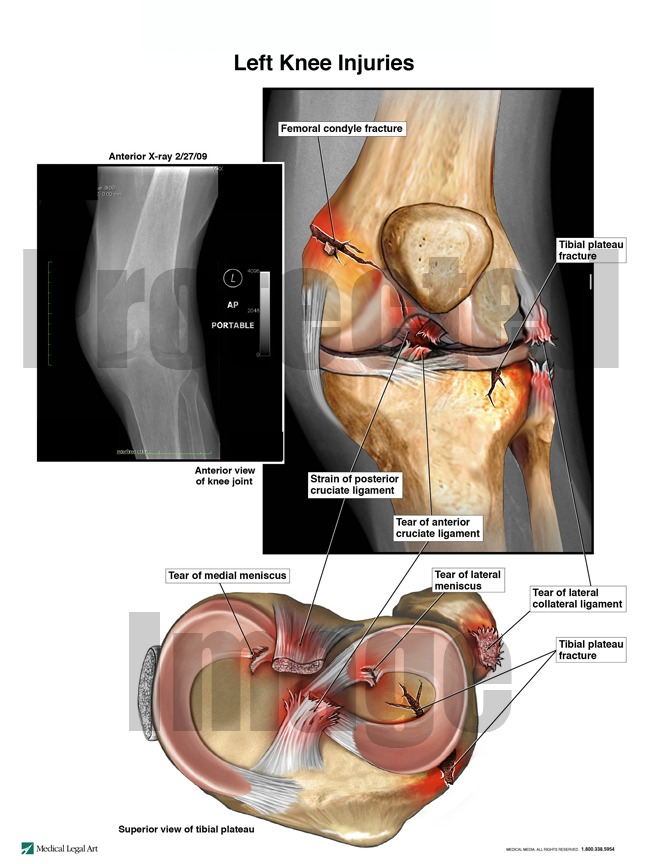

As a result of the fall, the patient sustained multiple fractures of the left leg and ligament tears of the left knee. After the fall, the patient was noted to scream in pain when her left leg was touched and when she was repositioned. The patient required powerful narcotics after the fall for pain management. The patient was a poor surgical candidate, so she received a knee immobilizer to stabilize the left leg fractures and other injuries. The patient’s orthopedist noted that the fractures had healed within two and one-half months after the fall, but the patient continued to experience decreased mobility. The patient died for reasons unrelated to the fall approximately one year later.